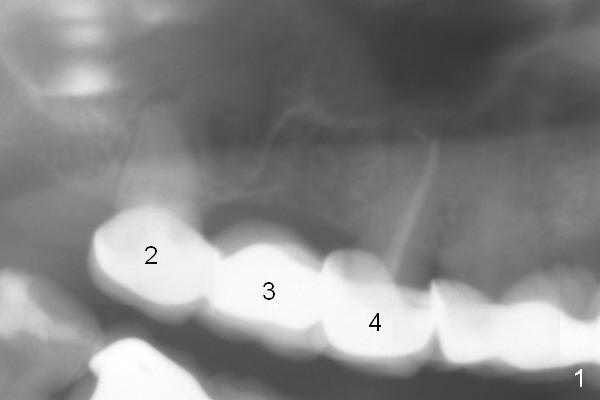

Posterior Maxillary Implants: As Short As Possible

A 47-year-old woman has multiple restoration. When #2-4 FPD ( is recemented, the 2 abutments are found nonsalvageable. To avoid sinus complications, implants at these 3 sites will be long enough, but do not penetrate the sinus floor unless primary stability cannot be obtained (Fig.2). Underprep is a must, particularly for immediate implants. Since the bone density at the site of #3 is low, bone expansion is to be conducted.